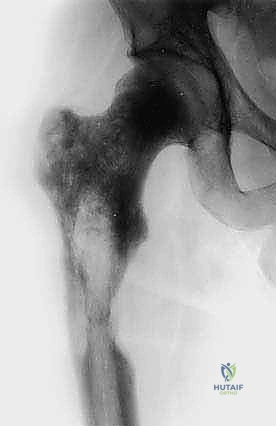

1. التثبيت الوقائي الداخلي (Prophylactic Internal Fixation)

إذا أظهرت الأشعة أن العظم ضعيف جداً وعلى وشك الانكسار، يقوم الدكتور هطيف بوضع أسياخ نخاعية معدنية (Intramedullary Nails) أو شرائح ومسامير متطورة داخل العظم لتدعيمه ومنع الكسر قبل حدوثه. هذه الجراحة الاستباقية توفر على المريض آلاماً مبرحة ومضاعفات خطيرة.

| عظم الفخذ (القسم العلوي) | كسر عنق الفخذ، العجز عن المشي. | استبدال مفصل الورك بمفصل صناعي (Arthroplasty). |

| جسم عظم الفخذ أو الساق | كسر مرضي كامل أثناء التحميل. | التثبيت بمسمار نخاعي تشابكي (Intramedullary Nailing). |